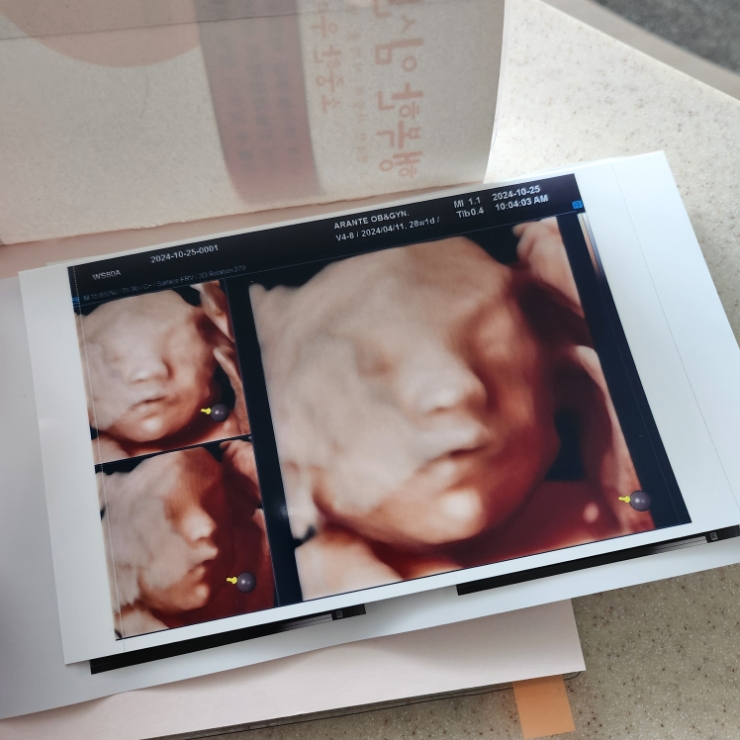

28w 1d 정기검진

입체초음파 찍는날 세상에 첫째랑 완전 똑같 애기가 태반에 얼굴을 파묻고 있어서 보기가 매우 힘들었는데 ...